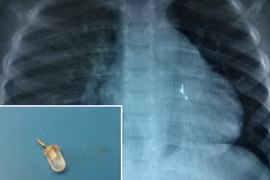

Viên nang “thám hiểm” đường ruột